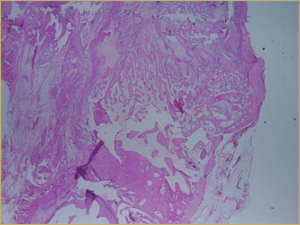

After 8 Weeks

By 8 weeks, all of the sinuses appeared histologically similar (Figs. 7–10). The mature lamellar bone that had been grafted in the autogenous bone group had been remodelled and was no longer present. Similarly, the numerous small-diameter woven bony trabeculae seen at 2 weeks in the BMP groups were no longer present. The sinuses all contained mature, small-diameter lamellar bony trabeculae. No qualitative histologic differences were apparent among the 5 treatment groups at 8 weeks (Figs. 7–10).

Figure 7: Low-power histologic examination of rabbit maxillary sinus augmented with autogenous bone graft at 8 weeks after procedure. H&E stain, 100× magnification.